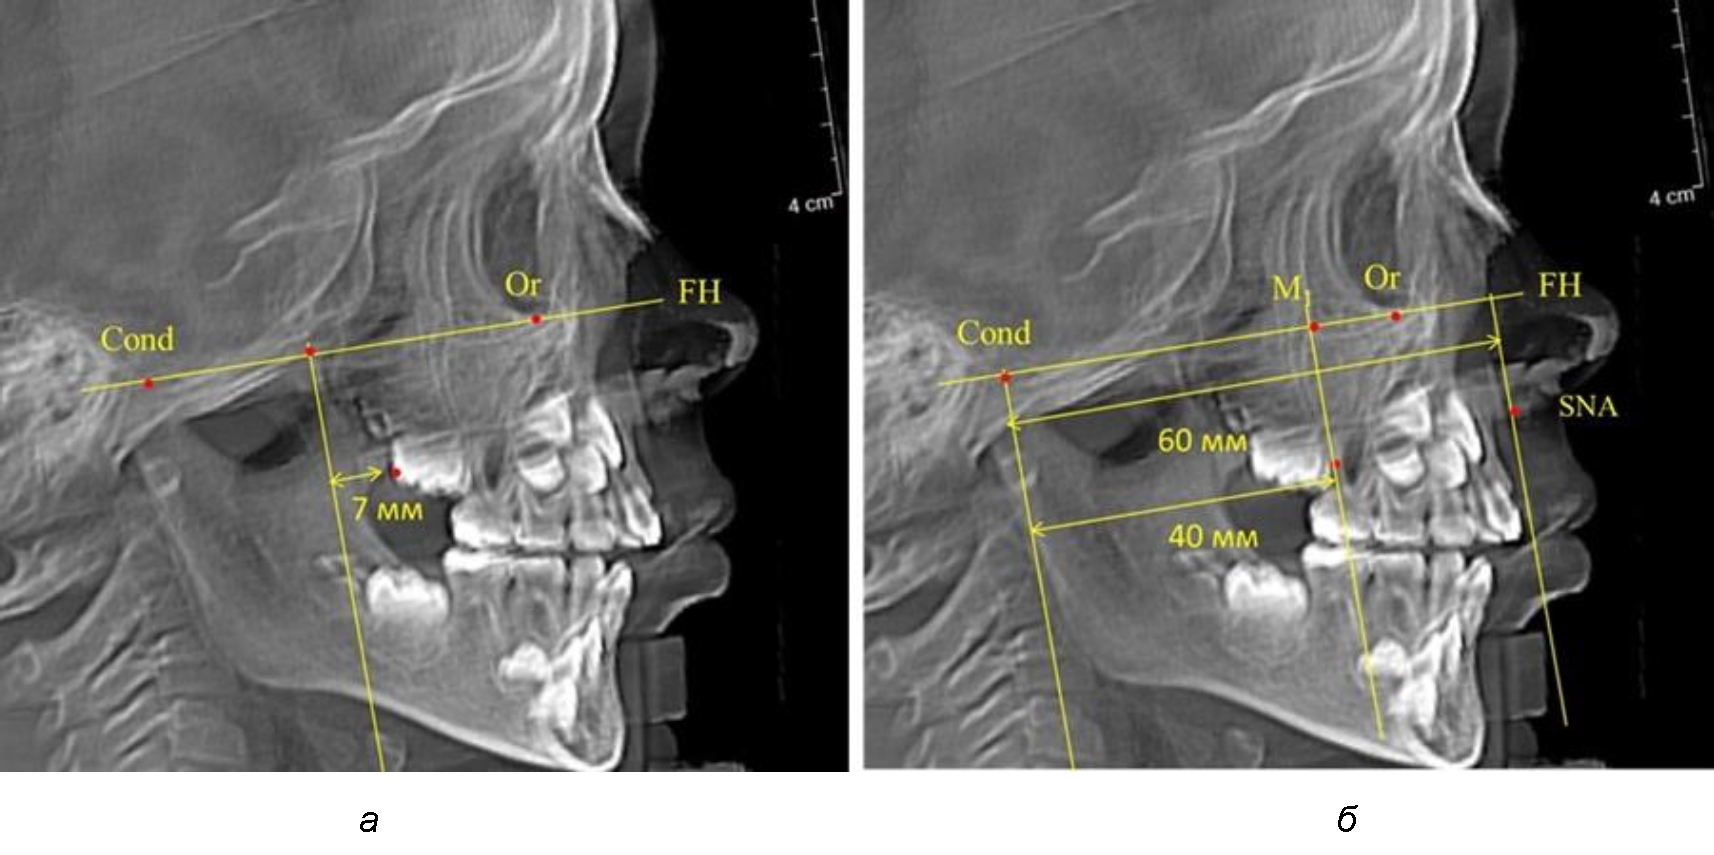

Так, при расстоянии от крыловидной вертикальной плоскости PTV до дистальной поверхности верхнего первого постоянного моляра в 13 мм сагиттальный размер гнатического отдела был 82 мм. При этом отношение кондилярно-спинального расстояния к кондилярно-молярному размеру (54,5) было близким к коэффициенту 1,5, что представлено на рис. 2.

Рис. 2. Особенности положения первых моляров по R. E. McDonald (а) и по предложенному методу (б) при уменьшенном молярно-крыловидном расстоянии